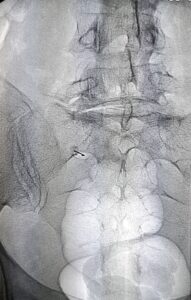

The insertion of the needle into the conjugation foramen, under fluoroscopic guidance, allows to reach the root affected by the pathological process. The target of the procedure is confirmed by the use of contrast liquid. The infiltration of the root with anti-inflammatory drugs, such as slow-release cortisone or ozone, allows the resolution of pain.